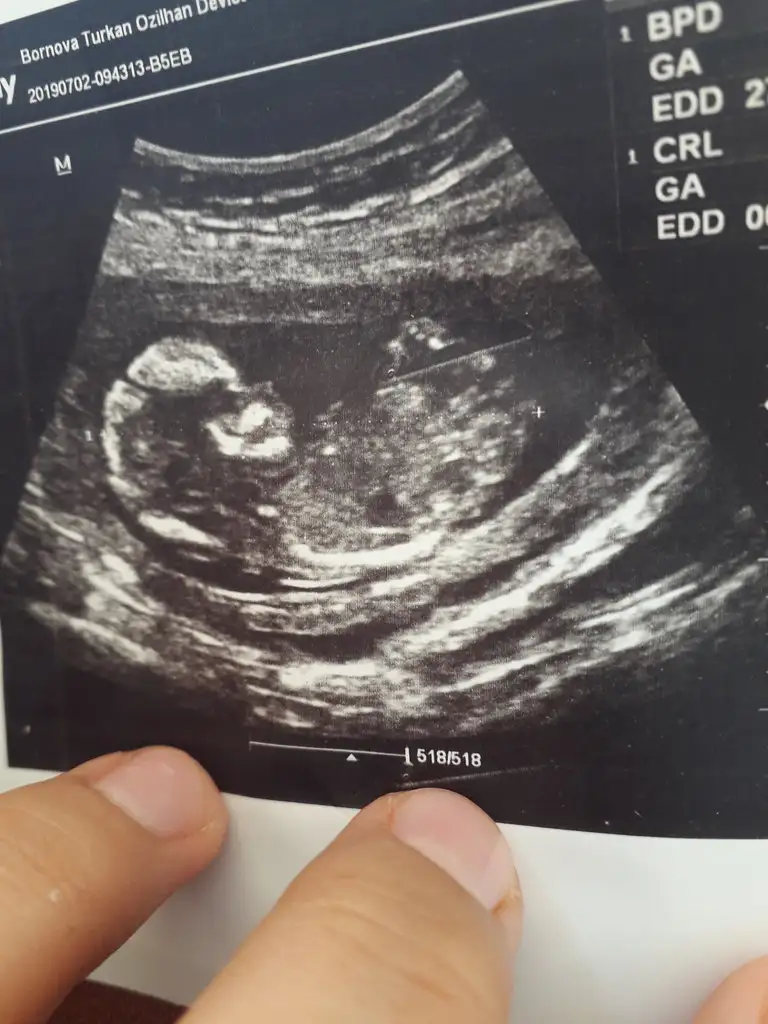

Merhaba arkadaslar bizede tahminlerinizi yaparmisiniz

Eklentiler

• 1554226393437-1558718618.webp

7,8 KB · Görüntüleme: 158